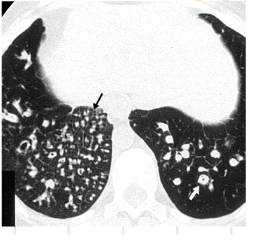

弥散性泛细支气管炎(DPB)是一种几乎仅亚洲人患病的进行性肺部炎症性病变,HRCT表现为小的小叶中心结节和树芽征(小叶中心结节与分支样线状影相连)等。

弥散性泛支气管炎CT图像

9.闭塞性细支气管炎

HRCT表现有中央性和周围性支气管扩张、支气管壁增厚,呼气末HRCT扫描有空气潴留是发现闭塞性细支气管炎的最敏感征象,此外还可见黏液嵌塞引起的小叶中心结节和树芽征。

闭塞性细支气管炎:高分辨率CT表现包括中枢和外周支气管扩张,支气管壁增厚。呼气相高分辨率CT是闭塞性细支气管炎检出最敏感的方式。